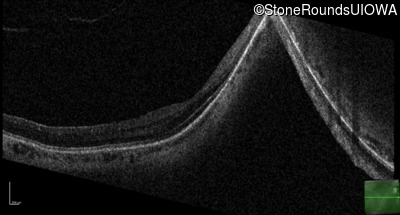

Age at visit: 41 years (Visit 2)

OD OS

This 41 year old woman was highly myopic as a child and experienced a rhegmatogenous retinal detachment OS at age 20.

Refraction OD:     -17.25 +1.00 x 93

Refraction OS:     -18.25 +3.50 x 56

The clinical features favoring the diagnosis of Sticker syndrome in this patient include extensive radial lattice degeneration, a personal and family history of rhegmatogenous retinal detachment, a history of cataract surgery before age 30 (and very high myopia before that), arthritis in her knees and hips and a slightly flattened mid-face.